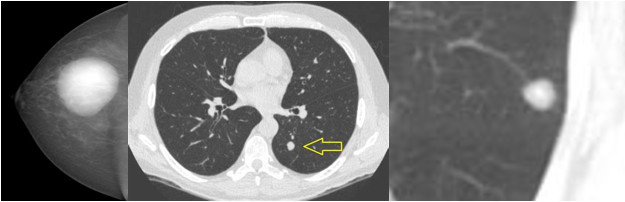

图片(胃癌患者术后复查的影像记录)

再看看这位远端胃癌患者,因为术后常规定期复查,在术后半年检查时发现在肝右叶有一个新发的很小的结节,我们就给他做了射频治疗,都不用手术,射频完了之后过了一年,这一片就坏死了,没什么活性了,现在三年多了患者活得非常好。所以早发现、早治疗很重要。

图片(患者术后复查的影像记录,肝上的大片阴影皆为转移灶)

相反的,像这两位患者,左图是乳腺癌患者的,术后一年半才复查;右图是结肠癌患者的,也是一年半以后复查,结果一看满肝都是转移,这个时候再治疗就比较困难了。当然我们也有各种药物,但是效果肯定没有及时发现的好。